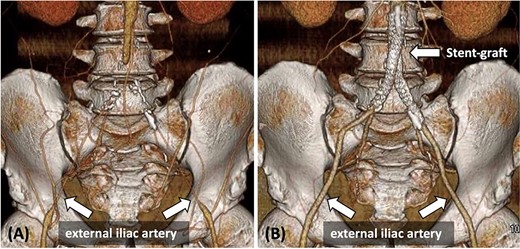

A 48-year-old man with a history of hypertension, dyslipidemia, and hyperuricemia presented with intermittent claudication for 50 m in both lower limbs. His body mass index (BMI) was 31.7 kg/m2. The patient’s right and left ankle-brachial index (ABI) values were 0.40 and 0.32, respectively. Contrast-enhanced computed tomography (CT) revealed complete bilateral common iliac artery (CIA) occlusion from the abdominal aorta at the inferior mesenteric artery (IMA) level (Fig. 1A). Furthermore, CT revealed bilateral EIA stenosis (right, 4.3 mm; left, 4.4 mm) without calcification or atheroma (Fig. 1A). He was diagnosed with AIOD with EIA stenosis, and was administered endovascular treatment because he was obese.

(A) Pre-operative contrast-enhanced CT reveals bilateral CIA occlusion from the abdominal aorta, with bilateral EIA stenosis, without calcification. (B) Contrast-enhanced CT 8 months post-surgery shows good bilateral EIA dilatation.

On post-operative day 2, the patient exhibited an ABI value of 0.99 in both lower limbs, recovered well, and was discharged. Eight months post-surgery, contrast-enhanced CT revealed no stenosis, and both EIA diameters improved (right: 8.3 mm, left: 7.5 mm) (Fig. 1B).